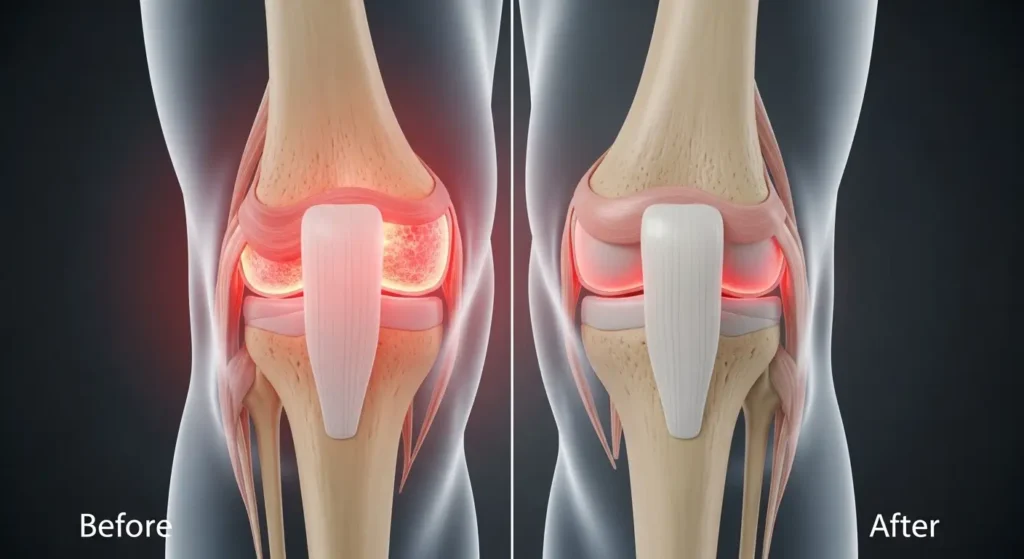

1. Powerful Relief for Osteoarthritis ⭐ PRIMARY BENEFIT

Clinical Evidence:

Boswellia benefits for osteoarthritis are among the most well-documented, with multiple clinical trials showing significant improvements.

Key Studies:

Knee Osteoarthritis:

- Study (2003): 333mg boswellia extract 3x daily reduced pain by 65% in 8 weeks

- Participants showed 50-70% improvement in pain, stiffness, and function

- Effects comparable to common arthritis medications

- Research in Phytomedicine confirms effectiveness

Multiple Joint Osteoarthritis:

- Study: 100mg AKBA-enriched boswellia showed significant improvement

- Reduced cartilage breakdown markers

- Improved physical function scores

- Well-tolerated with minimal side effects

Mechanism:

- Inhibits 5-LOX enzyme (blocks leukotriene synthesis)

- Reduces inflammatory cytokines in joints

- Protects cartilage from degradation

- May slow disease progression

Timeline: Most patients notice improvement within 4-8 weeks, with maximum benefits at 8-12 weeks of consistent use.

Dosage for Osteoarthritis: 300-500mg boswellia extract (standardized to 30-65% boswellic acids, with AKBA) 2-3 times daily = 900-1,500mg total daily